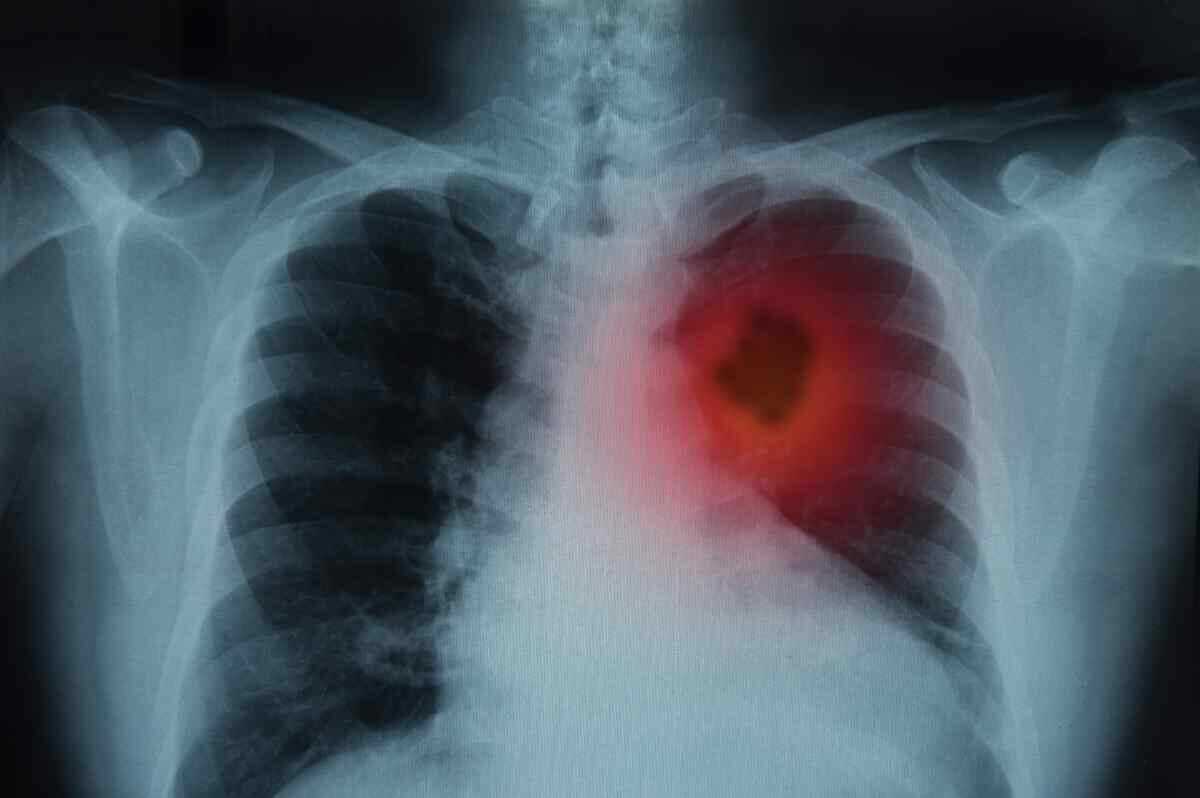

Akciğer vücudumuzun oksijen gereksinimini sağlayan organımızdır. Her organ gibi akciğerimiz de birçok hücreden oluşur. Bu hücreler akciğerin normal olarak görevini yapabilmesi için ihtiyaç doğrultusunda bölünerek çoğalırlar. Akciğer kanseri, yapısal olarak normal akciğer dokusundan olan hücrelerin ihtiyaç ve kontrol dışı çoğalarak akciğer içinde bir kitle (tümör) oluşturmasıdır. Burada oluşan kitle öncelikle bulunduğu ortamda büyür, daha ileriki aşamalarda ise çevre dokulara veya dolaşım yoluyla uzak oranlara yayılarak (karaciğer, kemik,beyin vb. gibi) hasara yol açarlar. Bu yayılmaya metastaz adı verilir.